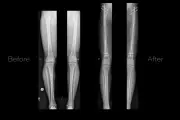

NHS Surgeries at Risk Due to Bone Cement Supply Crisis

Thousands of NHS hip and knee replacement surgeries could be delayed or cancelled due to a critical shortage of bone cement, caused by a packaging fault at a major supplier. The NHS is scrambling to find alternatives as patients face extended waits.